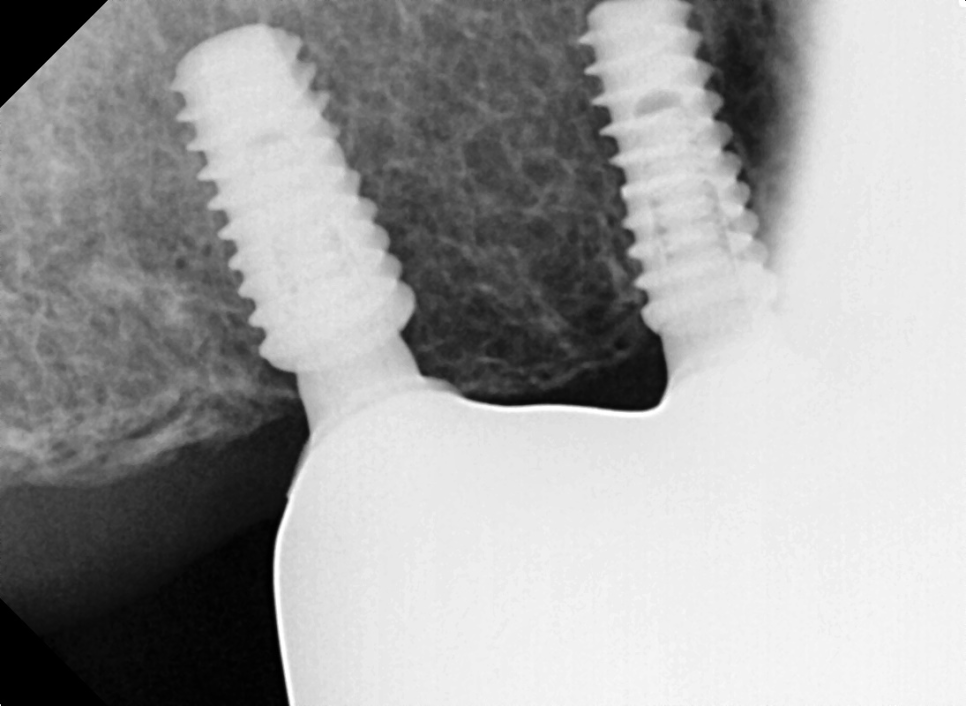

식립 이후의 파노라마 사진입니다.

수술 당시 골질은 D2정도로 상악임에도 단단하였고, 초기 고정은 각각 50N, 30N 이상, ISQ 또한 최대 80 가까이 나왔습니다.

최종보철물을 올리고 나서 찍은 엑스레이입니다.